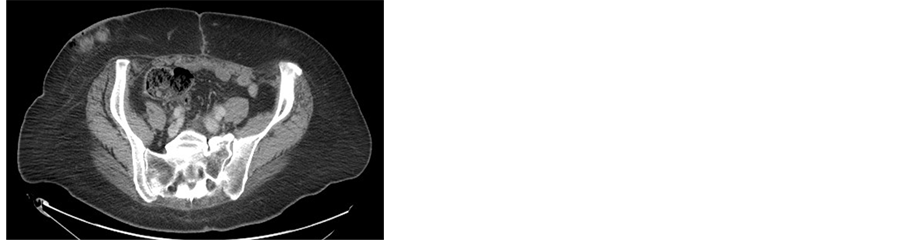

(a)(b)(c)(d)

Figure 5. (a) Incarcerated hernia; (b)-(d) CT scan of the abdomen shows metastases in the subcutaneous tissue in the sites of the laparoscopic ports.